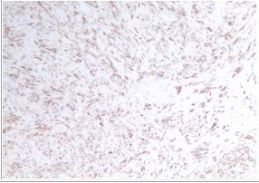

病理明确,真相大白

经HE染色及免疫组织化学检测,IHC:CD10(灶区+),Vimetin(+),ER(2+),PR(0),S-100(-),SMA(部分+),WT1(-),CD34(灶区+),Caldesmon(-),Des(+),Ki-67(1%+),CD117(-),Dog-1(-)。双侧附件未见特异性病变。腹水检查未查见异常细胞。

图4:Desmin

图5:SMA